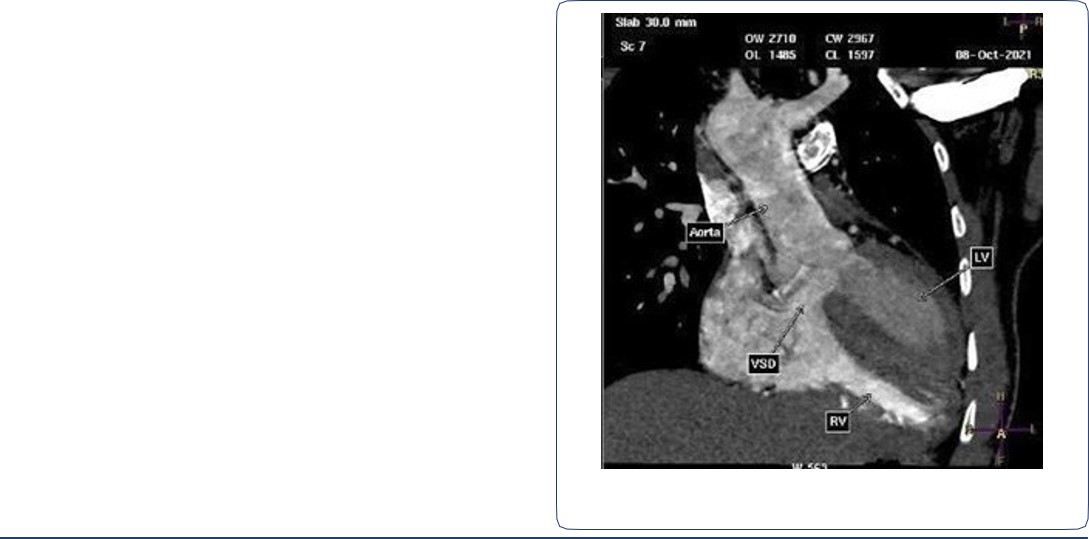

CT angiogram of chest shows complex cardiac disease including right-sided aortic arch (Figure 1), ventricular septal defect and overriding aorta (Figure 2). Non-visualization of the pulmonary trunk (Figure 3).

Two arterial supplies to the right lung arising from the descending aorta. A dominant one arising from the medial side that supplies the right upper lobe (Figure 3). Another smaller branch supplies the right middle and lower lobes (Figure 4).

Right ventricular dilatation with myocardial hypertrophy (Figure 4).

Figure 2: Contrast-enhanced reconstructed 3 chambers view of the heart showing a ventricular septal defect and overriding aorta.

Figure 3: Contrast-enhanced CT chest axial (A), sagittal and coronal (B) views, showing an arterial supply to the right upper lobe arising from the descending aorta. Also there is an absent left pulmonary artery with multiple small collaterals at the left hilar region. Relative hypo-plastic left lung.